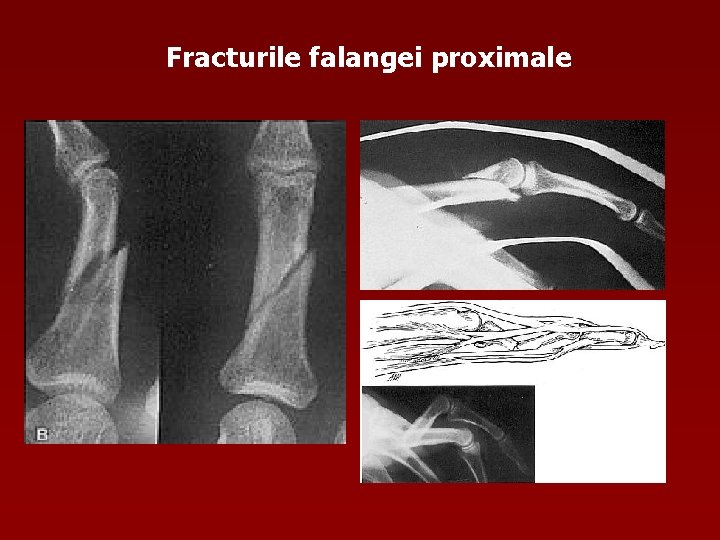

Fracturile falangei proximale